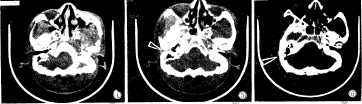

图1 CT薄层重叠平扫显示颅前窝蝶骨小翼斜行骨折和颅中窝两处骨折并移位。图2 CT薄层重叠平扫显示筛板横行骨折及左眶板斜行骨折。图3 CT薄层重叠平扫未发现骨折线。图4 显示右颞骨岩部一斜行走向的骨折线。图5 显示右侧岩骨与鼓室盖向前成角折裂。图6 仅显示右颞骨一斜行细密骨折线(图3、4、5、6为同一患者连续薄层重叠扫描成像)。

虽然颅底骨CT平扫空间有限,但通过薄层重叠扫描法增加扫描层数,可反映出骨折病变全貌,适于颅底骨创伤疾病的应用(图3)。图3~图6可见一完整的骨折线。这种比较完整的连续成像不仅为具有手术指征的脑脊液耳或鼻漏、颅底神经受压、反复脑膜炎发作且高度怀疑颅底损伤者选择手术入路提供极有价值的影像学依据,而且对临床全面分析病情以及估计预后有着重要指导意义。